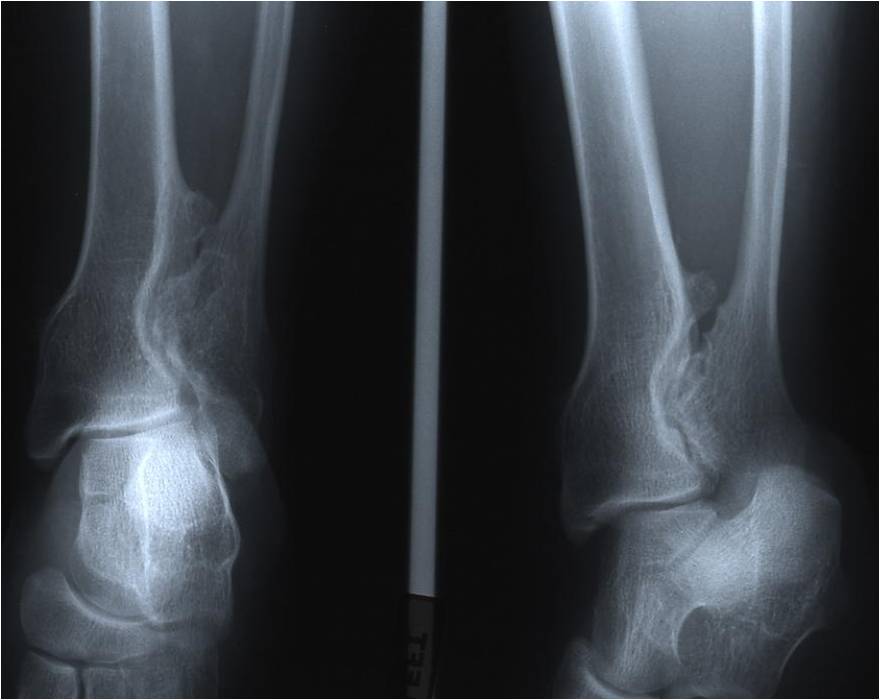

Dysplasia Episphysealis Hemimelica – Trevor Disease

- Male predominance (3:1)

- Very rare < 100 cases

- Swelling, pain and deformity

- Usually lower extremity, unilateral

- 65% multiple done involvement: talus, distal femur, tibia

- Ankle and knee most common

- Medial joint 2X lateral

- Lobular epiphyseal mass

- Histologically identical to an osteochondroma

- May produce deformity and secondary osteoarthritis